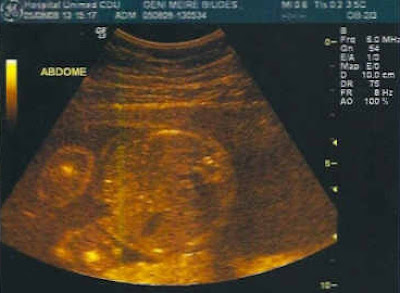

O barrigão (que não é igual ao do pai)